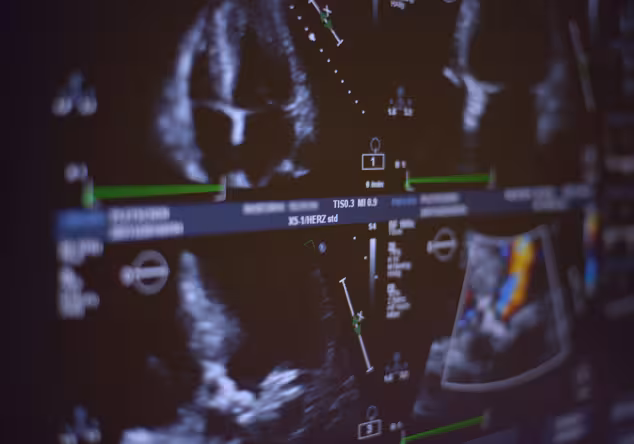

In der Regel überprüft der behandelnde Arzt die Funktionalität der neuen Herzklappe direkt nach dem Eingriff mit einer Ultraschalluntersuchung.

Echokardiogramm auf einem Monitor